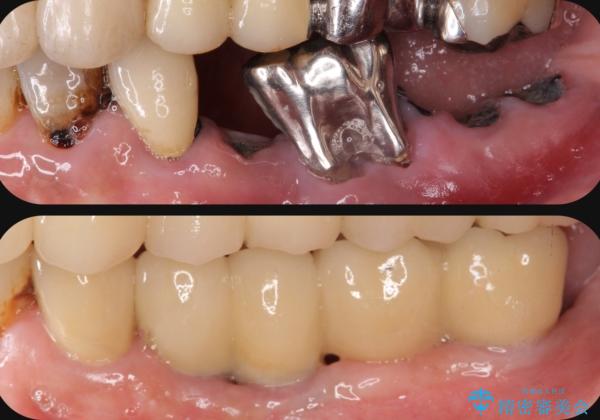

虫歯による歯の喪失 インプラントによる咬合機能回復

- 深い虫歯や歯の破折、多数の問題を口腔内に抱えて来院されました。

虫歯の徹底的な除去、安定した噛み合わせを達成するインプラント治療、深い虫歯、根管治療といった複数の治療項目を一つづつ積み重ね、長期的な予後を目指します。

複雑な問題点に対する明確な治療目標を立てることで、最終的に長い予後を期待できる治療を達成することができます。